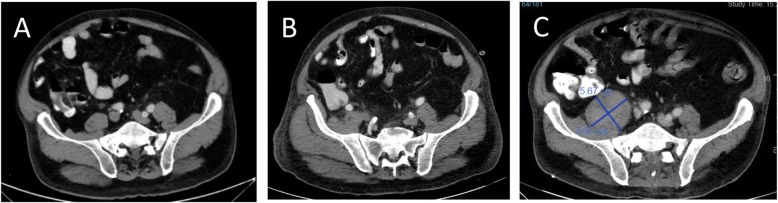

On day 6 post-ERCP, the antibiotic regimen was changed to Ertapenem and Vancomycin, to treat possible multi-drug resistant pathogens. Two days later, extended-spectrum beta-lactamase positive Klebsiella Pneumonia and Enterococcus Hirae were identified on blood cultures so antibiotics were switched to Imipenem and Cilastatin. Nonetheless, the patient continued to have abdominal pain. Upon examination, his abdomen was soft and distended, with no signs of peritonitis. CRP was elevated (160 mg/L), with mild leukocytosis (13 x 10e3/uL) and neutrophilia (83%). CT scan, with a double contrast of the abdomen and pelvis was repeated on day 7 post-ERCP revealing a hypodense irregular lesion that was found to increase in diameter, this finding was consistent with pyogenic liver abscess (Fig. 1b). Also, a hypodense lesion in the right psoas appeared (Fig. 2b), which was not seen on the first CT scan (Fig. 2a), it was decided to continue with antibiotic treatment without drainage. Two days after the antibiotic regimen was changed to Imipenem and Cilastatin, the abdominal pain subsided. He was afebrile and his liver function tests and bilirubin normalized. However, on day 10 post-ERCP, the patient began to complain about low back pain and difficulty walking. On physical examination, he had localized tenderness over the spinous processes of L4-L5, and reduced quadriceps femoris strength (3/5). A thoracolumbar spine magnetic resonance imaging (MRI) scan was recommended by a consulting orthopedic surgeon to evaluate for possible myelopathy or radiculopathy. MRI was performed on day 19 post ERCP, which revealed L4-L5 discitis,a large iliopsoas abscess on the right side,and other small abscess on the left side, an epidural abscess in front of spinal canal at level L1-D11 other one at level L2- S1 appearing to compress the spinal cord (Fig. 3). A diagnosis of spinal epidural abscess (SEA) with discitis and osteomyelitis was established. The patient was transferred to the orthopedic department and was urgently operated. Decompressive laminectomy of L5 was done and a large epidural abscess was drained and irrigated. Drainage catheters were placed, and the wound was closed in layers. Cultures from the pus were positive for Klebsiella pneumonia. Thus, IV antibiotics with polymyxin E and Gentamicin were initiated Post-operatively, and the patient’s back pain significantly subsided. Nonetheless, due to continued of serosanguineous drainage from the surgical incision, fever of 38.7C, CT total body was performed on day 7 postoperative to evaluate epidural and liver abscess, exhibited a 4.8 cm hypodense irregular lesion at segment 7 of the liver,epidural and psoas abscess were increased in size (Figs. 1c,2c). patient was taken back to the operating room for other evaluation. The decompressive laminectomy was expanded to include L2-L4, and multiple irrigations were done. Gentamycin and Vancomycin containing polymethylmethacrylate beads were implanted locally and drainage catheters were placed before wound closure. The patient was continued intravenous antibiotics with polymyxin E and Gentamicin. Two days later the patient was presented to the multidisciplinary panel (surgery and radiology) for further evaluation and discussion of liver and iliopsoas abscess treatment options. In light of the clinician and laboratory improvement it was decided to continue with a non invasive approach and to complete 6 weeks of antibiotic treatment. During the subsequent days the patient’s condition improved, the surgical incision was inspected without signs of infection or leak, and his lap tests normalized. Two months later,abdominal and spinal cord CT scan was performed as part of the follow up examination which assured almost complete regression of liver and iliopsoas abscess. An interval cholecystectomy was performed 6 weeks after discharging.